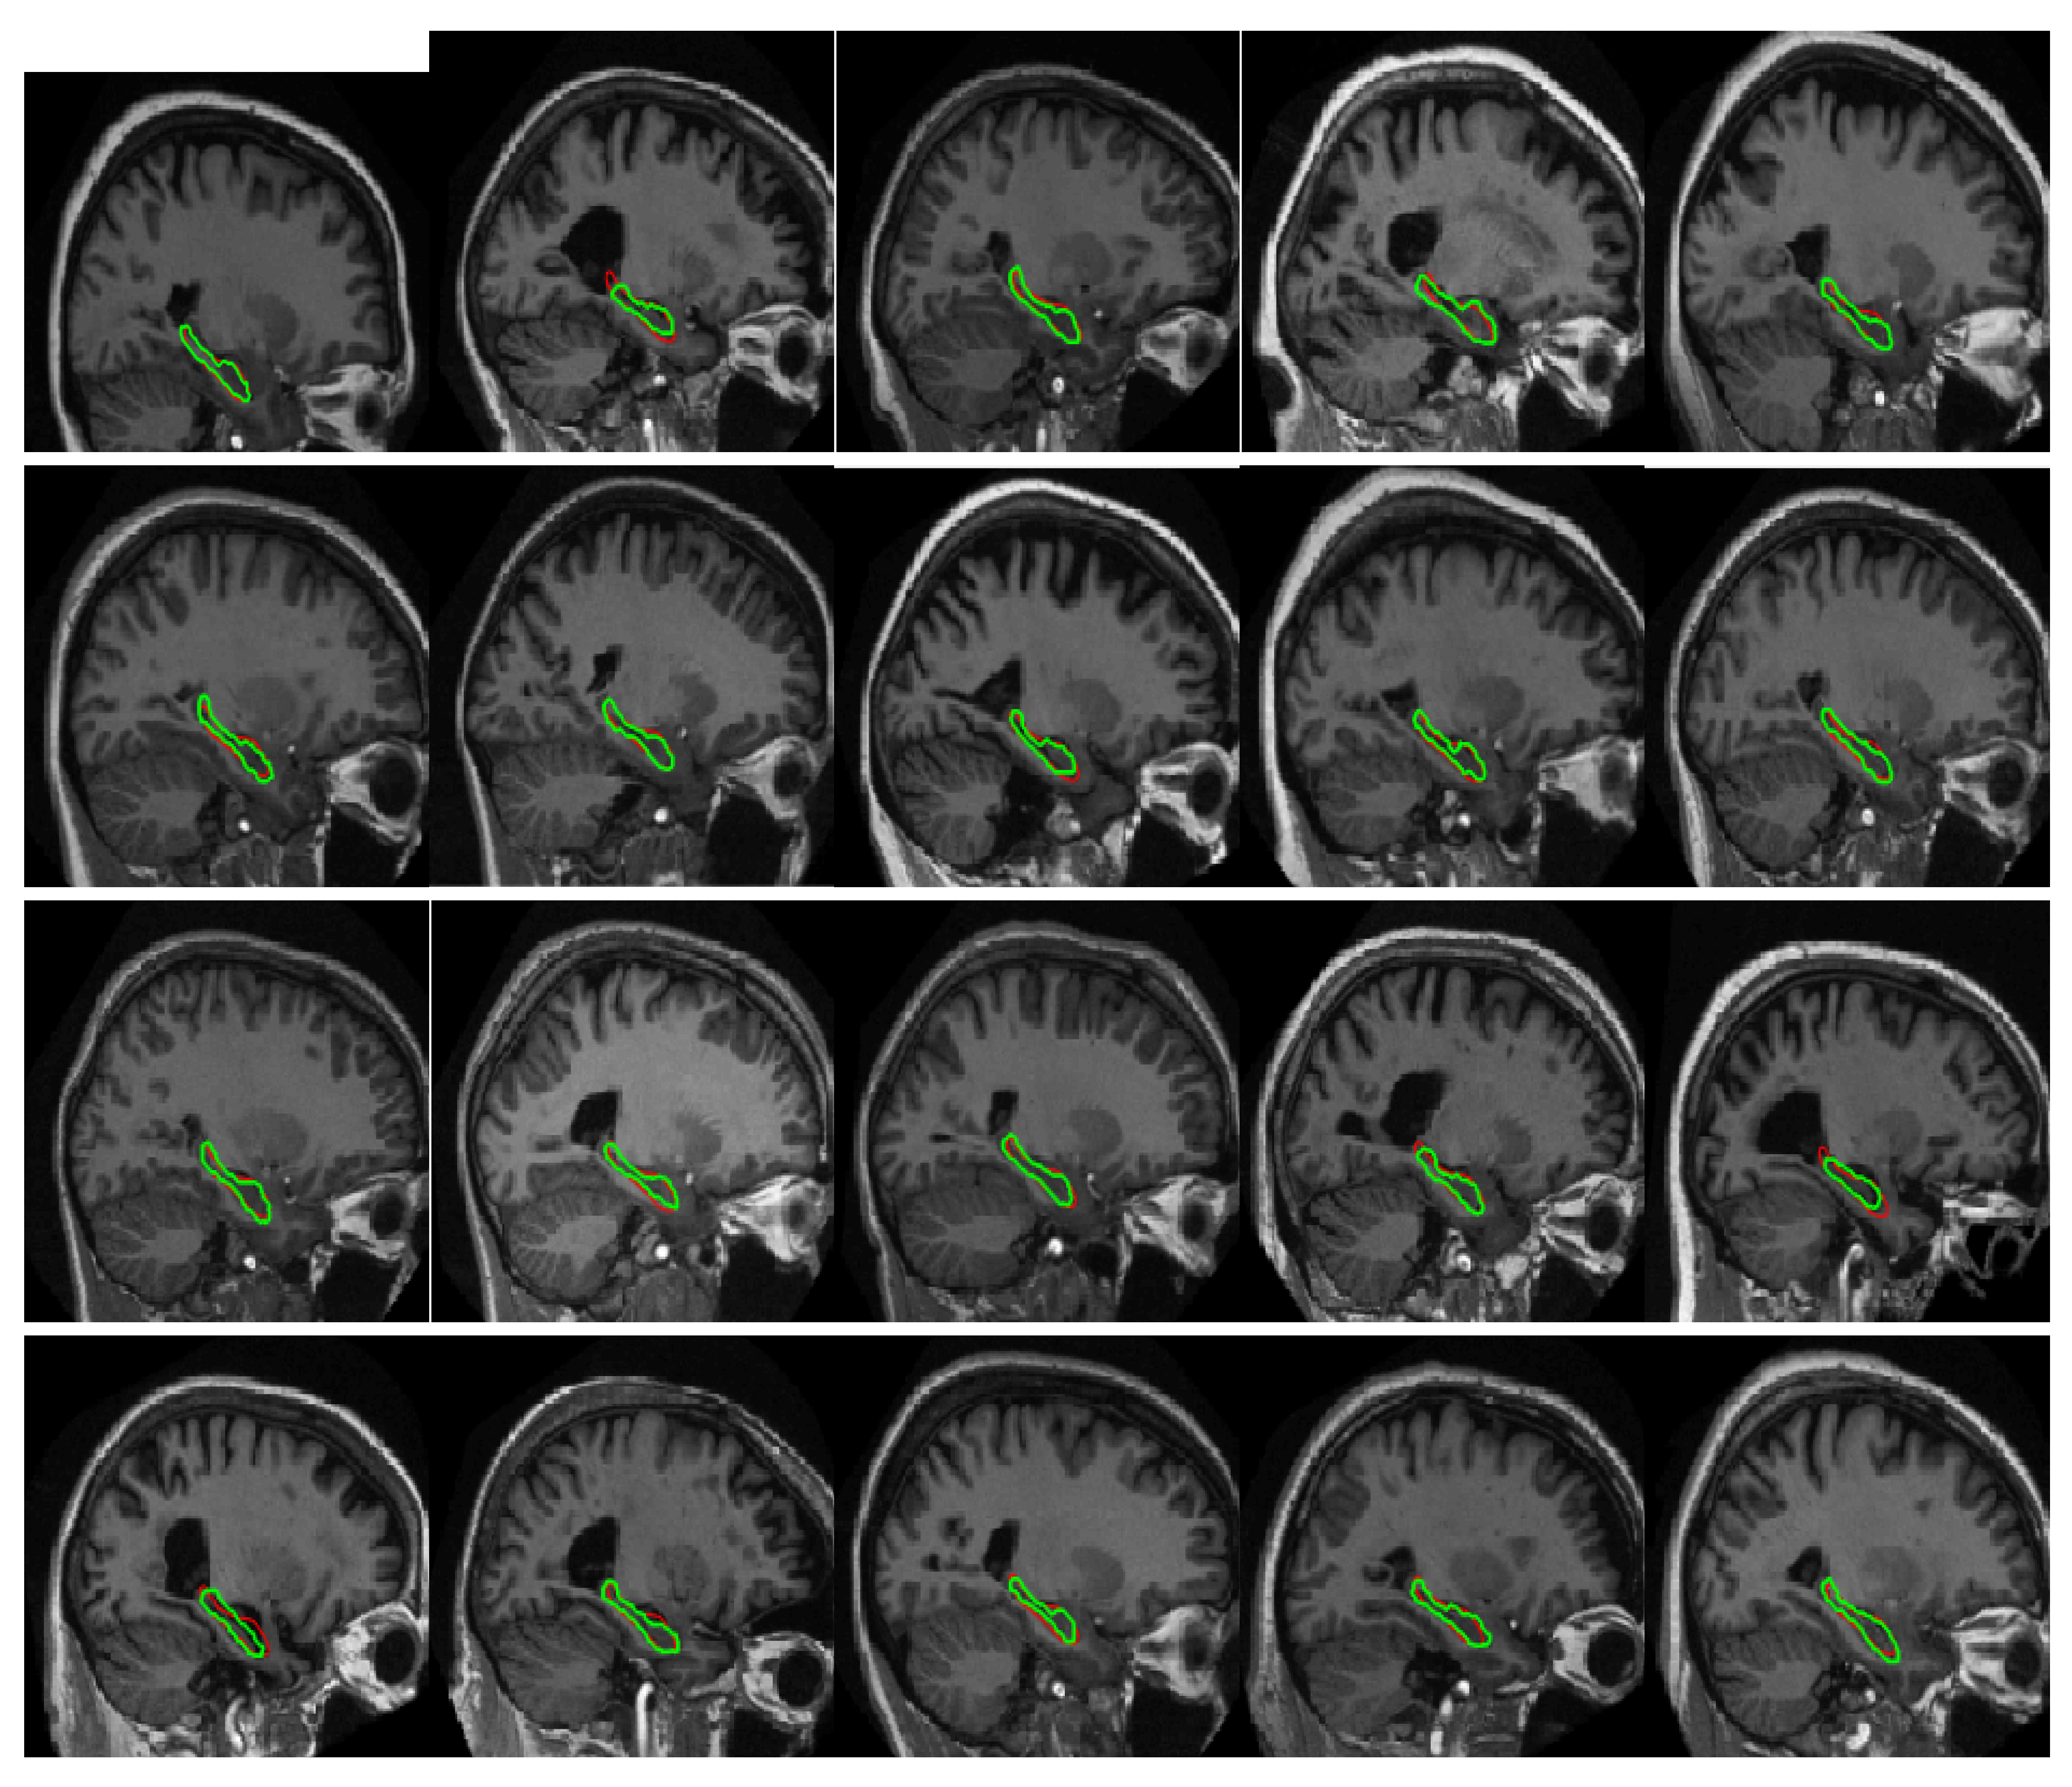

4.2.2. Experiments on Hippocampus Images

4.3. Comparison with Other Methods